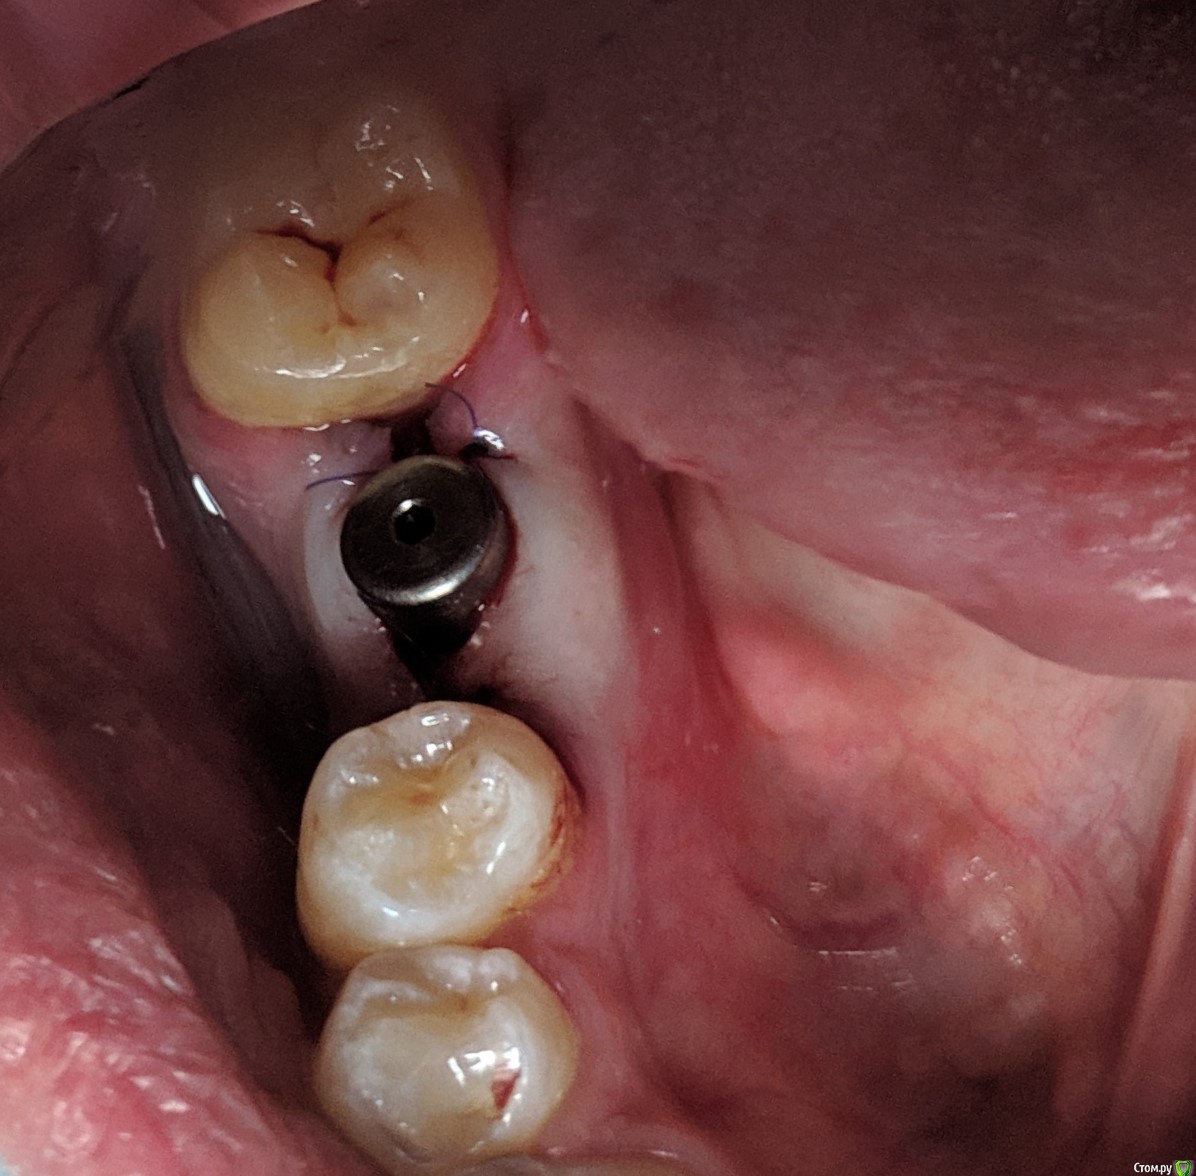

MP1121 Опубликовано 4 августа, 2020 Автор Поделиться Опубликовано 4 августа, 2020 Вопрос возник из-за спора с коллегой. Он считает что в конкретном случае необходимо было добавлять кость. Никакие доводы, в пользу того что ширины более чем достаточно,не принимаются. Аргументирует тем что будет эстетический(!) дефект, и нормальную коронку сделать нельзя. Имплант уже поставил Ссылка на комментарий

MP1121 Опубликовано 4 августа, 2020 Автор Поделиться Опубликовано 4 августа, 2020 Понимаю) пПциент, позвонил мне после консультации ортопеда в другой клинике, спросил почему ему даже не предложили костную пластику. Ну думаю ок, пациент что-то напутал, бывает, успокоил, попросил номер врача, созвонился и в ответ тоже самое... Я сказал что вестибулярно от шейки импланта кости миллиметра 3, и над платформой 4-5 мм. десны. Предложил узнать мнение коллег и дать ему ссылку на форум. КТ после операции не делали, но сейчас хочу направить.Не претендую на звание виртуозного хирурга, да и практикую всего два года, но такая ситуация очень неприятна. Ссылка на комментарий

колесников Опубликовано 5 августа, 2020 Поделиться Опубликовано 5 августа, 2020 Ортопед оценивает с учетом будущей реставрации. Относительно моляра есть дефицит объёма гребня,но для имплантации объём костной ткани достаточный. Данный дефицит нивелируется дополнительной пластикой мягких тканей вестибулярно и земной с узкого на широкий фдм. Но мне кажется ,вы слишком язычно сместили платформу , и теперь решить проблему заменой на более широкий но стандартный фдм ,будет не просто,придётся делать индивидуальный. 1 Ссылка на комментарий